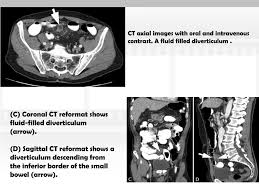

Ct For Acute Nontraumatic Abdominal Pain Is Oral Contrast Really Required Sciencedirect